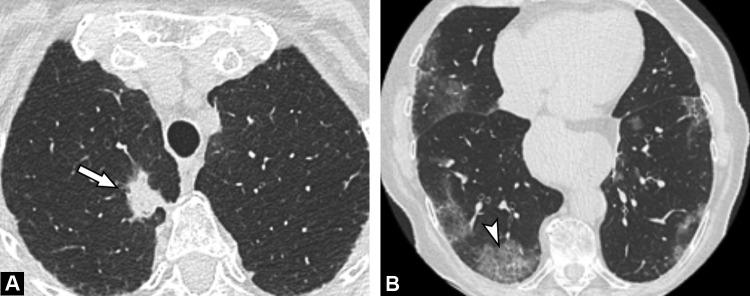

During the study period, among 205 diagnostic CT examinations, six examinations (6/205, 3%) in 6 different patients (4 men, 2 women; median age, 57 years) revealed images highly suggestive of COVID-19 pneumonia. The final diagnosis was confirmed by RT-PCR. Three inpatients were suspected of extra thoracic infection whereas three outpatients were either fully asymptomatic or presented with fatigue only. All had increased CRP serum level and lymphopenia. Disease extent on CT was mild to moderate in 5/6 patients (83%) and severe in 1/6 patient (17%).

Cumulative incidence of fortuitous diagnosis if COVID-19 pneumonia did not exceed 3% during the highest pandemic phase and was predominantly associated with limited lung involvement.